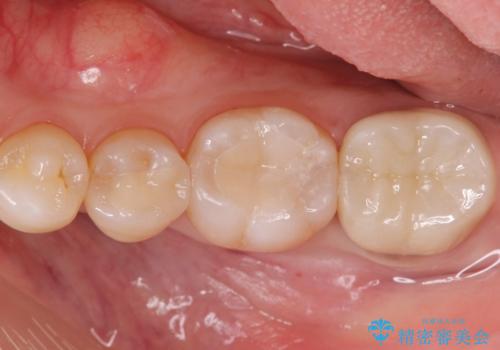

劣化して黒くなりたくない、虫歯の予防がしたいとのご希望だったのでセラミックインレー(e-maxインレー)による治療を行いました。

プラスチック樹脂は安価で治療時間も一回で終わるが歯質との隙間ができやすく虫歯の再発のリスクが高いです。また、吸水性なので何年か過ぎると劣化します。

セラミックは歯質との隙間ができにくく虫歯の再発のリスクをさげ劣化防止にもなります。